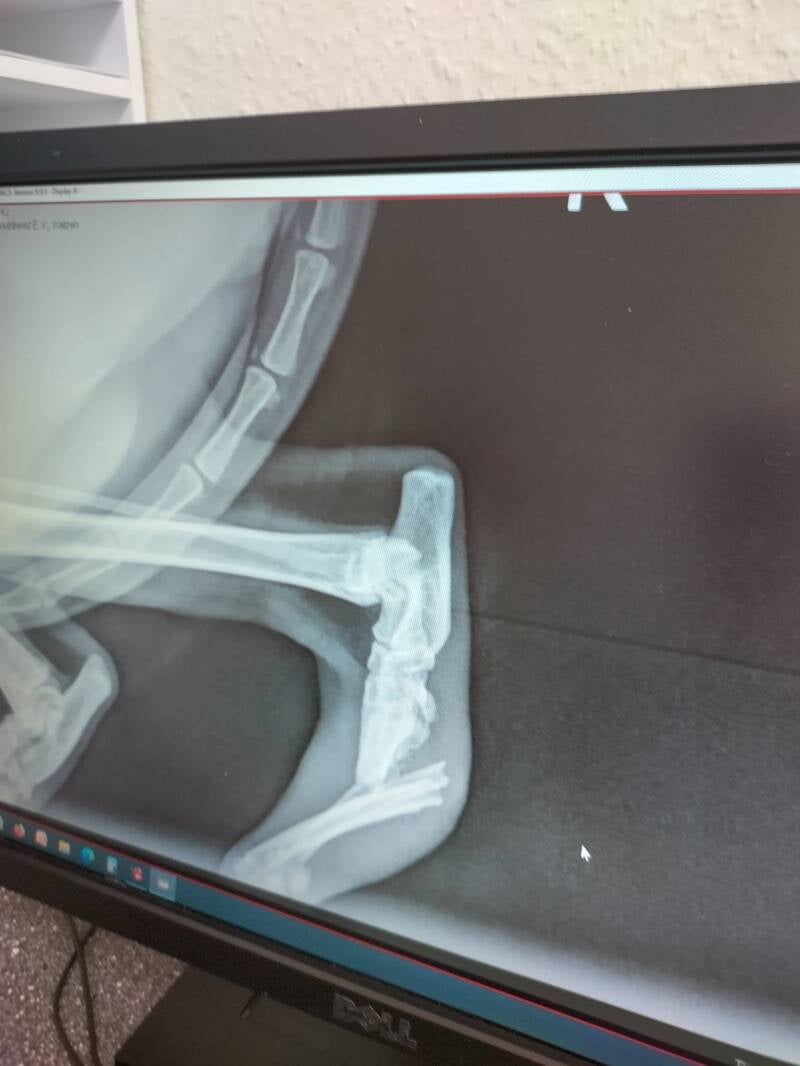

Verletzte Tiere ärztlich Versorgen

Jede Katze wird von uns zum Tierarzt gebracht und dort komplett rundum versorgt. Kastrieren, Impfen, Chippen etc.